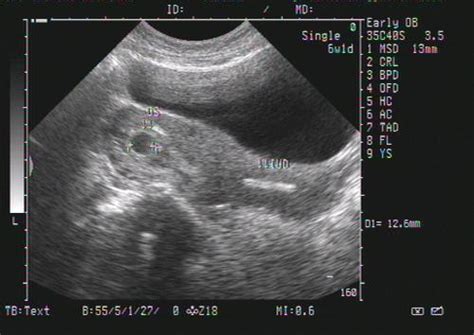

怀孕8个月的B超数据

根据孕周表,您的宝宝双顶径和骨长,也就是头部横径和大腿骨长都发育正常,胎心和羊水深度也在范围值内,脐带血阻比也正常。

不必担心,更不用提前剖腹产,完全可以顺产的。

怀孕8个月胎儿B超数据

10月28号应该是32周了。

胎儿发育正常,不要担心,预产期12月19,推迟1周也在正常范围内。

怀孕八个月B超结果如下:双顶径80mm.胎心率132次/分,股骨长59mm,羊水深约61mm,内透声好。胎盘附于子宫前壁,厚约28mm,绒毛板轻度起伏。这样正常吗,知不知道有几斤?谢谢

2000克左右!

31周左右,一切正常!